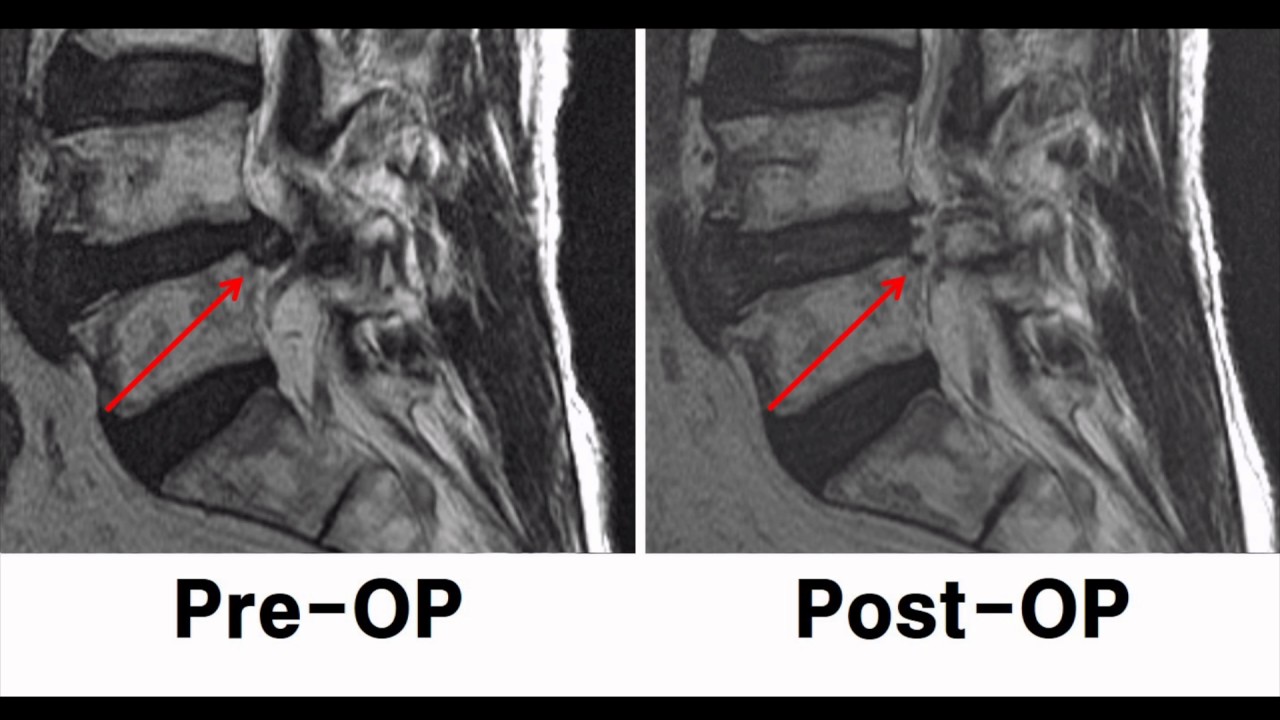

Lumbar Disc Herniation MRI Explained Dr. Jeffrey P. Johnson HD Lumbar Disc Herniation Youtube Ebraheim’s educational animated video describes low back pain. Among the many differential diagnoses of lbp, degenerative disc disease and lumbar disc herniation (ldh) are the most common. This is a common condition, and most people do not experience any symptoms. Approximately 95% of disc herniations in the. If you have a herniated disk — also referred to as a slipped,. Lumbar Disc Herniation Youtube.